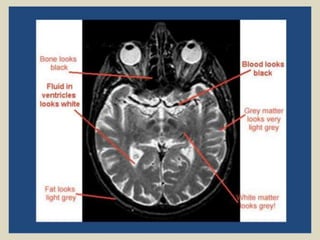

Magnetic resonance imaging (MRI) was discovered in 1947 by two physicists and the first clinical images were obtained in 1977. MRI uses strong magnetic fields between 1-9 Tesla to align hydrogen atoms in the body and radio waves to elicit signals to form images. The document provides a brief history of MRI and discusses magnetic fields, relaxation processes, and pulse sequences used to generate MRI images.